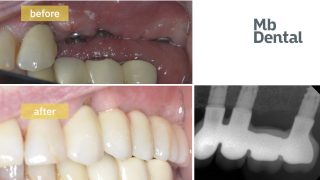

In anumite cazuri favorabile, medicul chirurg poate decide daca poate fi realizata o corona provizorie imediat dupa implant.

Investiţia dumneavoastră pentru un implant dentar din titan plus o coroana ceramică este de 4300 lei ( 2400 lei implantul dentar; coroana ceramica 1600 lei, iar surubul de conexiune dintre acestea 300 lei) şi se achită după fiecare etapă de tratament. Coroana dentară care se montează peste implant este realizată din cermanica pe schelet metalic şi se achită în momentul cimentării/insurubarii sale (la cateva luni după prima vizita).